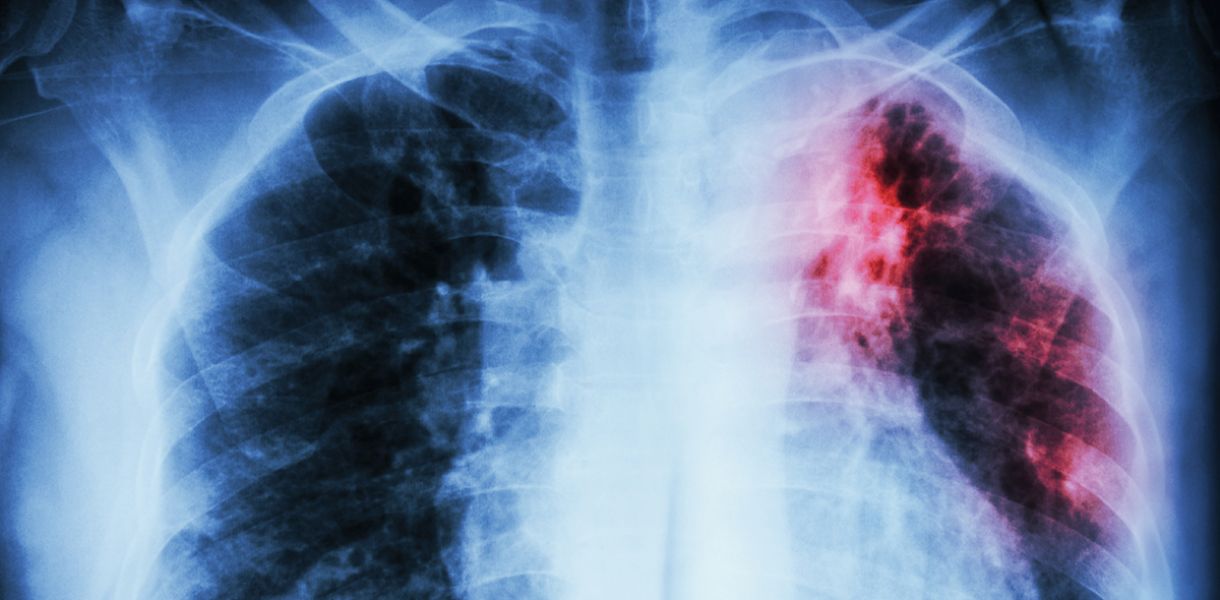

Открытая Форма Туберкулеза ФотоВЫБЕРИТЕ ВАШ ПОЛ👨 👉🏻👉🏻👉🏻МУЖЧИНА👈🏻👈🏻👈🏻👩🦱 👉🏻👉🏻👉🏻ЖЕНЩИНА👈🏻👈🏻👈🏻Открытая Форма Туберкулеза Фото (199 фото)